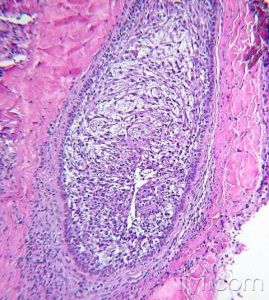

病理改變

蕈樣黴菌病2.結節硬化型(NS)HD:以雙摺光寬膠原纖維束,將存在腔隙型R-S細胞的淋巴組織分隔成大小不一結節為特徵,典型R-S細胞罕見。

3.混合細胞型(MC)HD:典型R-S細胞和H細胞多,炎性細胞明顯多形性,伴血管增生和纖維化。

4.淋巴細胞消減型(LD)HD:除存在典型R-S細胞外,還可出現許多多形性R-S細胞(網狀細胞型)或瀰漫性非雙摺光纖維組織增生,反應性炎性細胞顯著減少。